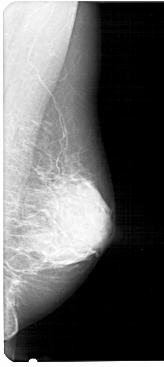

A_1280_1.RIGHT_MLO

RIGHT_CC LINES 5011 PIXELS_PER_LINE 2341 BITS_PER_PIXEL 12 RESOLUTION 43.5 NON_OVERLAY

RIGHT_MLO LINES 5491 PIXELS_PER_LINE 2446 BITS_PER_PIXEL 12 RESOLUTION 43.5 NON_OVERLAY